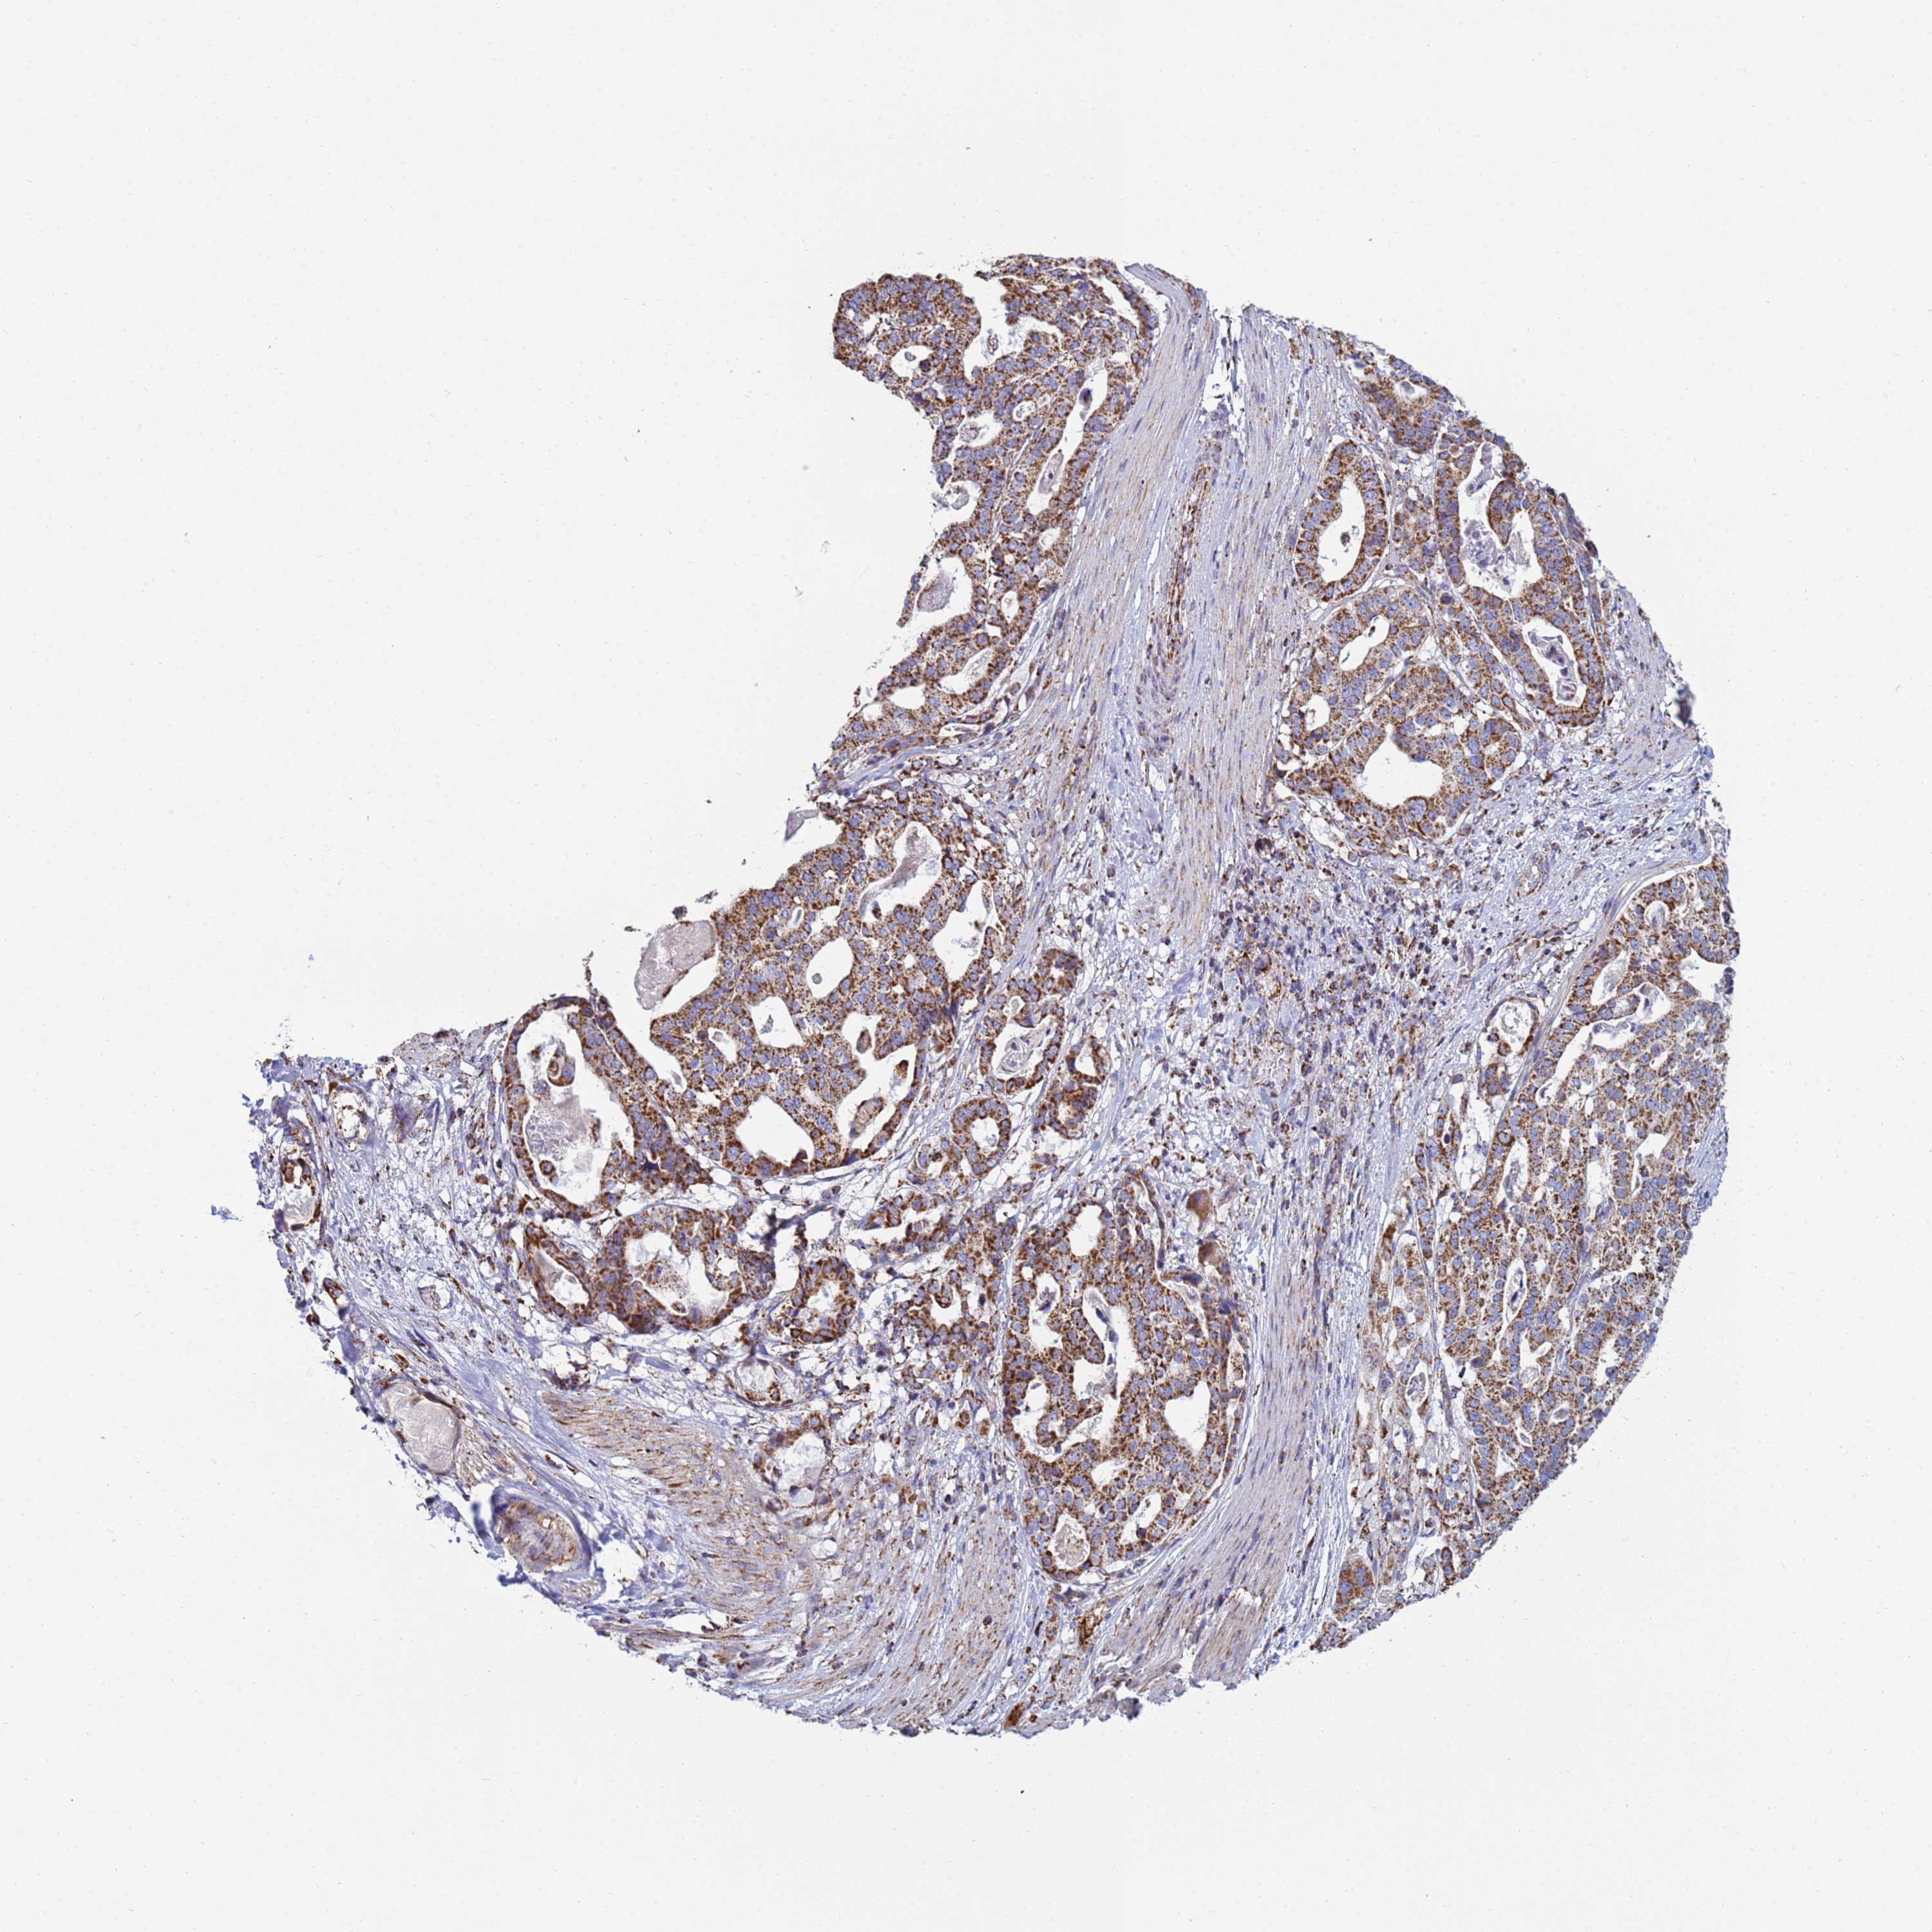

STOMACH CANCER - Protein expressioni

A mouse-over function shows sample information and annotation data. Click on an image to view it in a full screen mode. Samples can be filtered based on level of antibody staining by selecting one or several of the following categories: high, medium, low and not detected. The assay and annotation is described here.

Note that samples used for immunohistochemistry by the Human Protein Atlas do not correspond to samples in the TCGA dataset.

Antibody stainingi

Antibody staining in the annotated cell types in the current human tissue is reported as not detected, low, medium, or high, based on conventional immunohistochemistry profiling in selected tissues. This score is based on the combination of the staining intensity and fraction of stained cells.

Each image is clickable and will lead to virtual microscopy that enables deeper exploration of all samples and also displays staining intensity scores, fraction scores and subcellular localization as well as patient and tissue information for each sample.

Antibody HPA042945

Staining

High

Medium

Low

Not detected

Intensity

Strong

Moderate

Weak

Negative

Quantity

>75%

75%-25%

<25%

None

Location

Nuclear

Cytoplasmic/membranous

Cytoplasmic/membranous,nuclear

Adenocarcinoma, NOS